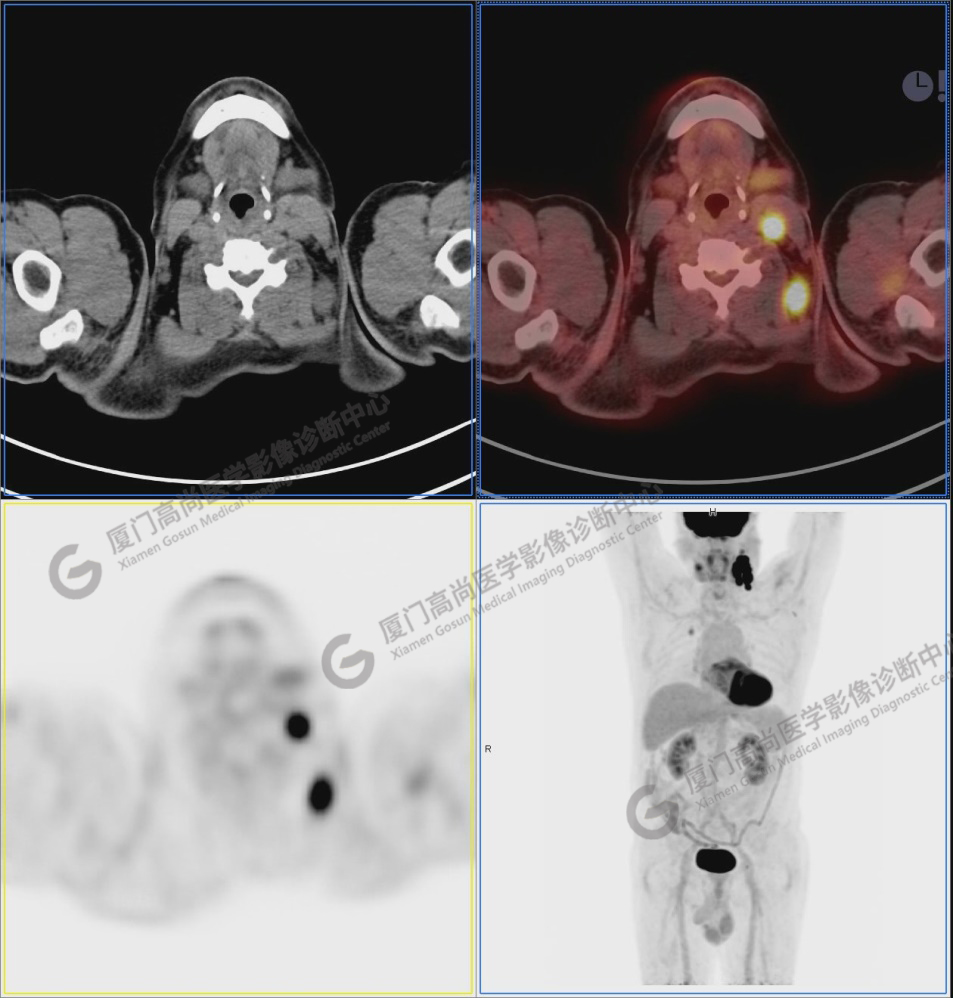

圖1:PET/CT全身圖像

圖2-9:雙側(cè)鎖骨區(qū)、縱隔、右側(cè)內(nèi)乳區(qū)、腸系膜緣、腹膜后、雙側(cè)髂血管旁及盆腔多發(fā)腫大淋巴結(jié)影,代謝不同程度增高,考慮為轉(zhuǎn)移。

圖2

圖3